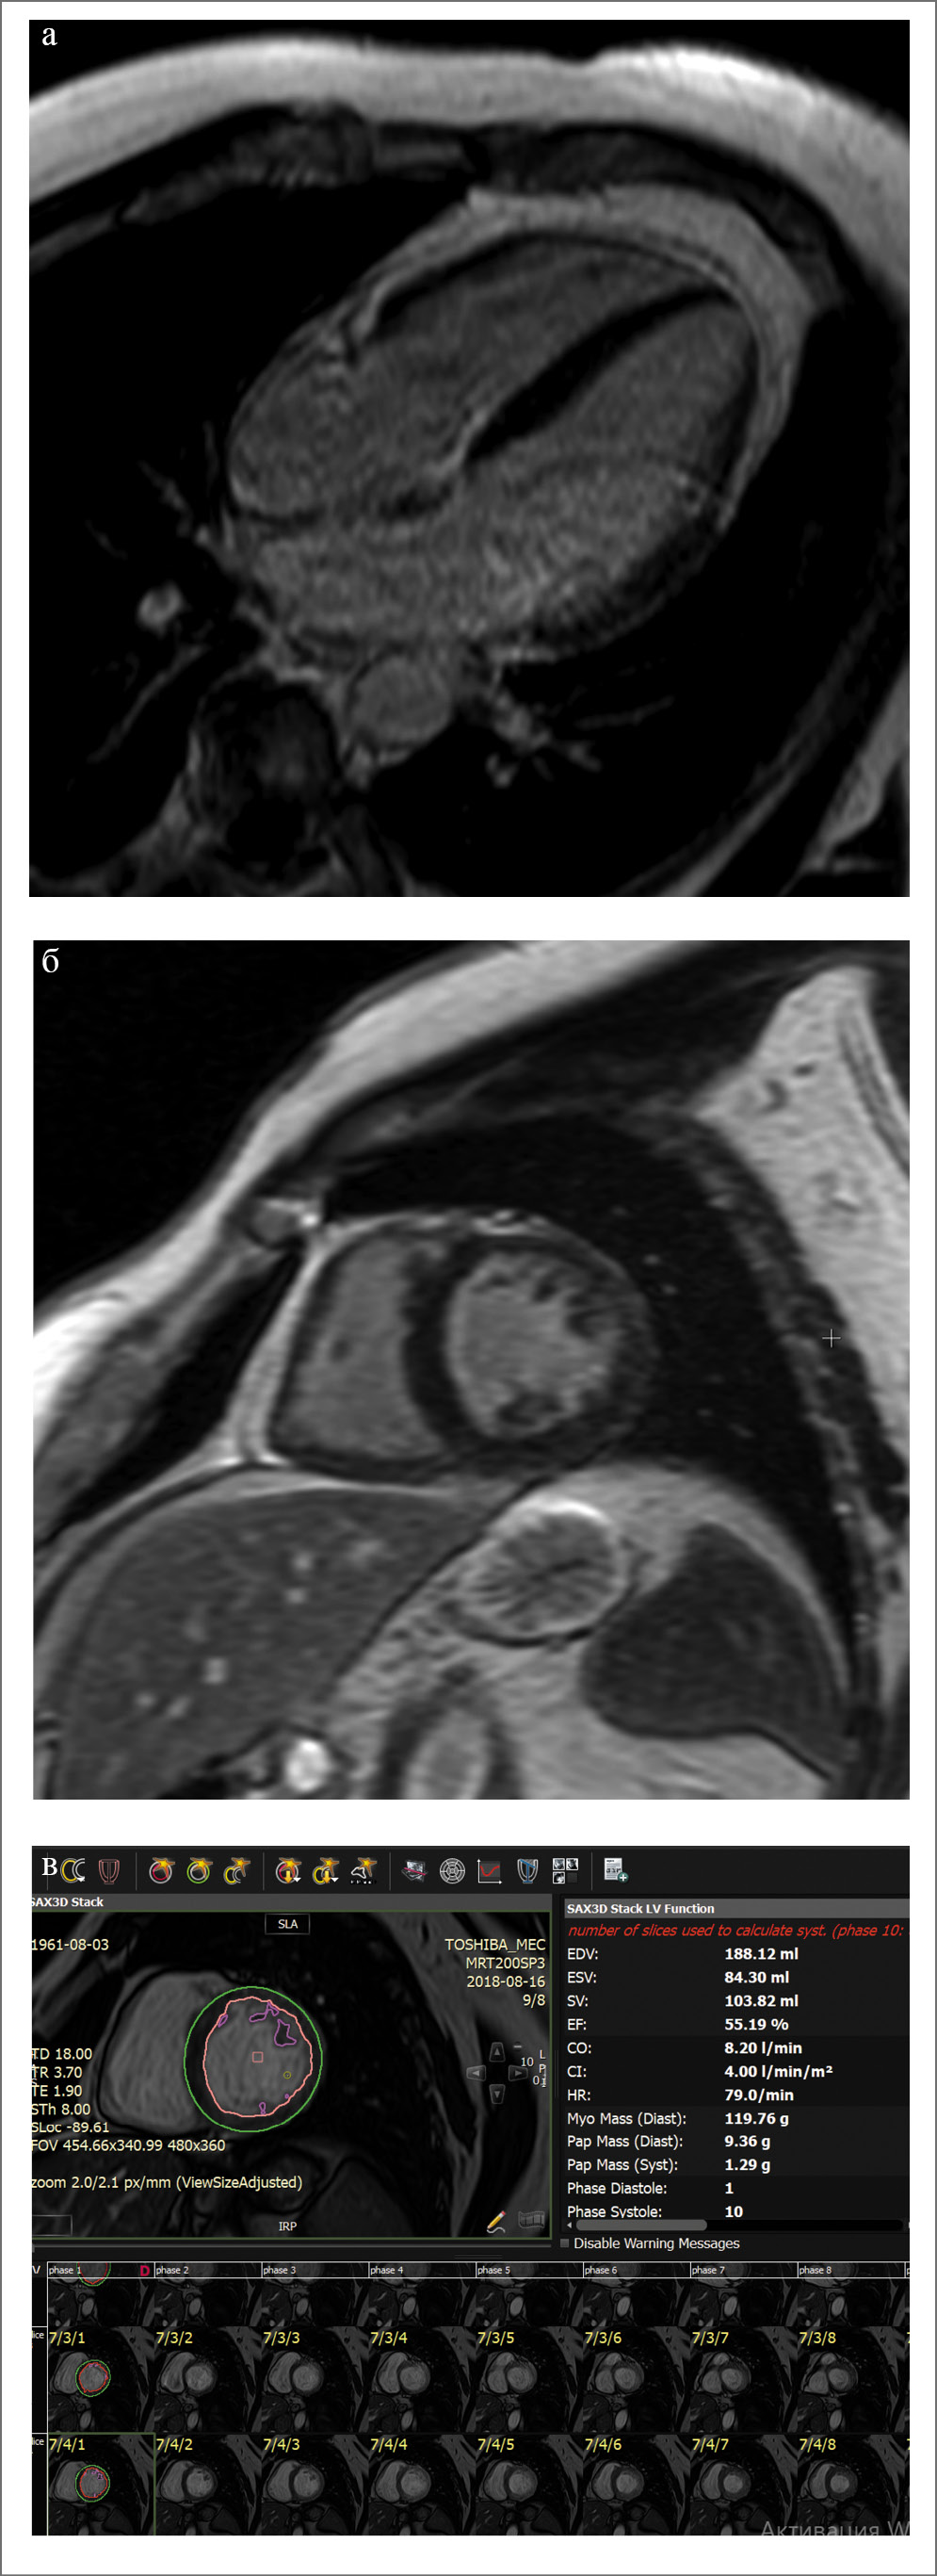

Спустя 5 нед с целью исключения структурной патологии миокарда пациенту проведена МРТ сердца, не выявившая каких-либо патологических изменений (рис. 5).

Рис. 5. МРТ сердца: а, б – отсутствие отсроченного контрастирования, в – сохранная ФВ

Отсутствие отсроченного контрастирования указывало на отсутствие структурных изменений миокарда (поствоспалительного фиброза, постишемических рубцов) и преимущественно «электрический» генез ХСН. При дальнейшем наблюдении явления ХСН не рецидивировали на фоне отмены диуретической терапии. В связи с выявленной артериальной гипертензией продолжается терапия ингибиторами ангиотензинпревращающего фермента и β-адреноблокаторами, амиодароном и ривароксабаном в дозе 20 мг. В данном случае показанием для длительного приема антикоагулянтов является как вторичная профилактика ТЭЛА, так и нарушения ритма (трепетание и ФП) при значении риска по шкале CHA2-DS-VAC 1 балл (артериальная гипертензия). Пациент смог вернуться к трудовой деятельности. В динамике через 4 мес после проведенного РЧА при суточном мониторировании ЭКГ по Холтеру у пациента в течение всего исследования определялся синусовый ритм с ЧСС 47–103 уд/мин, за сутки зарегистрировано 119 наджелудочковых экстрасистол. Пауз, нарушений ритма и проводимости не зарегистрировано.